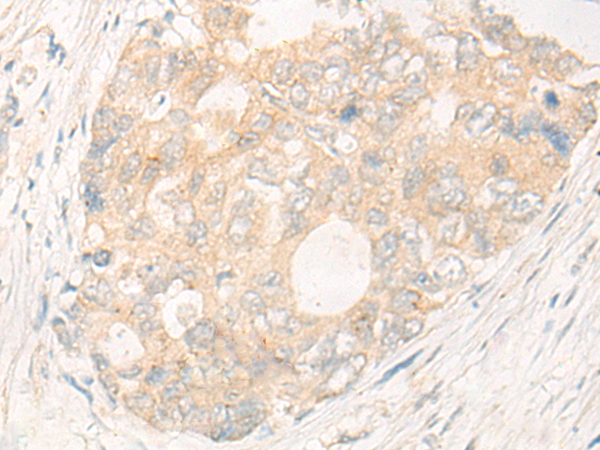

分类: 科研抗体货号: P06414别名:应用: IHC反应种属: Human